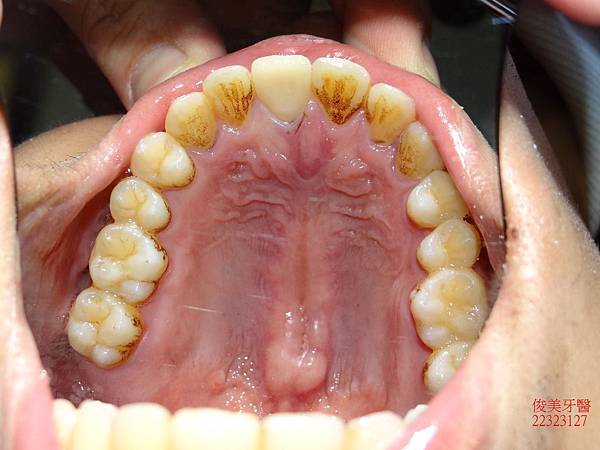

上顎牙弓形狀

下顎牙弓形狀